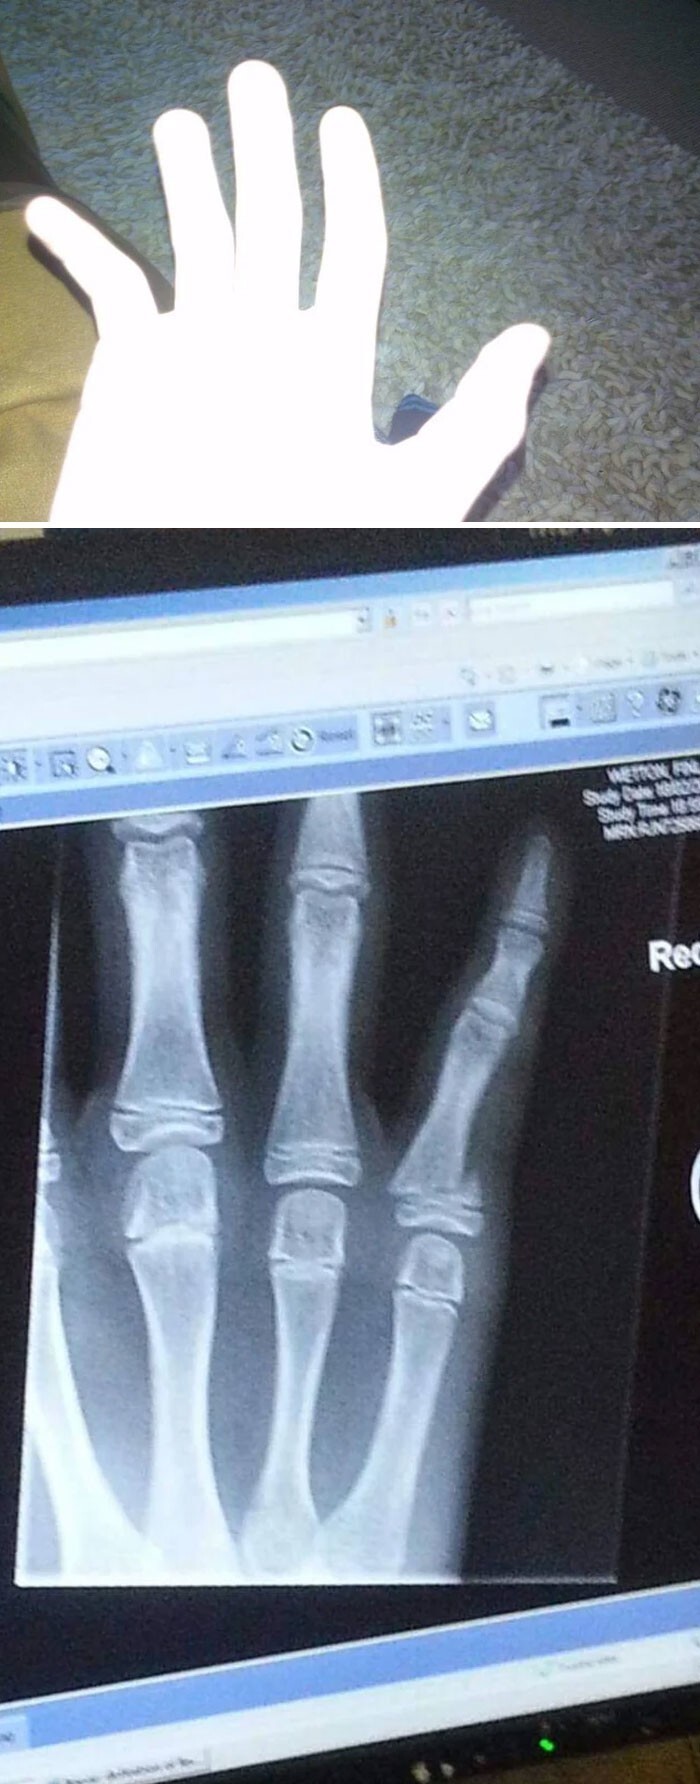

30. "Сломал палец в поисках чем бы перекусить"